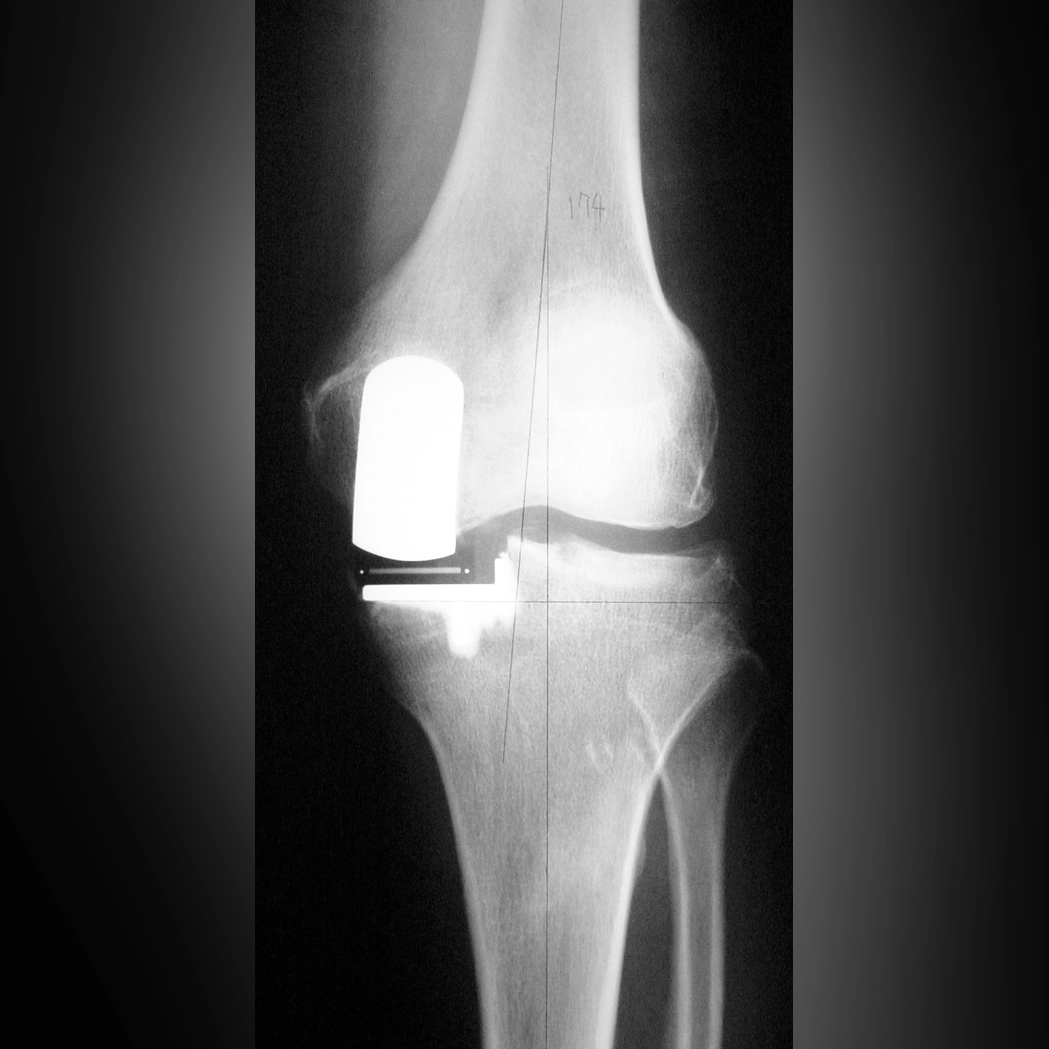

半置換術(UKA)

中期から末期前半においては、十字じん帯がまだ残っていることが多く、そうした方には半置換術(UKA)をおすすめしています。半置換術は、悪くなった内側のみを人工関節に置き換える手術で、十字じん帯を残すことが可能です。全置換術に比べて切開が小さく、筋肉を切らずにおこなえるため、術後の腫れが少なく、正座ができるほどひざを曲げられる方も少なくありません。さらに、十字じん帯が残っていることで、その緊張が脳にフィードバックされる(プロプリオセプション)ため、自然な感覚が保たれます。そのため、術後にひざが悪くなる以前にされていたスポーツに復帰される患者さんも多く見られます。